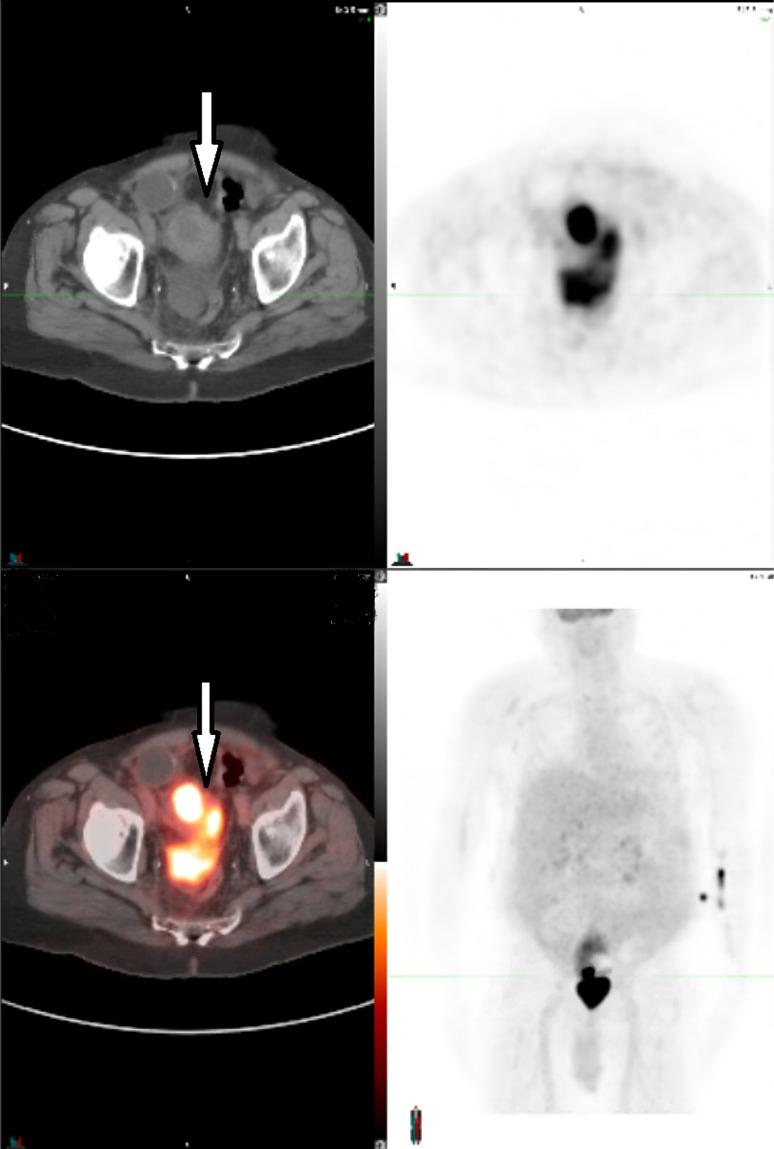

Case presentation: Here, we present a case of a male with liver disease with portal hypertension, a previous history of cancer, and prior surgery with an artificial urinary sphincter placement who developed acute recurrent ascites and rapidly progressing acute kidney failure requiring dialysis. Extensive workup revealed that the kidney failure was caused by SBR, resulting in urinary ascites. The bladder rupture was treated by surgery, leading to complete resolution of the patient's symptoms.